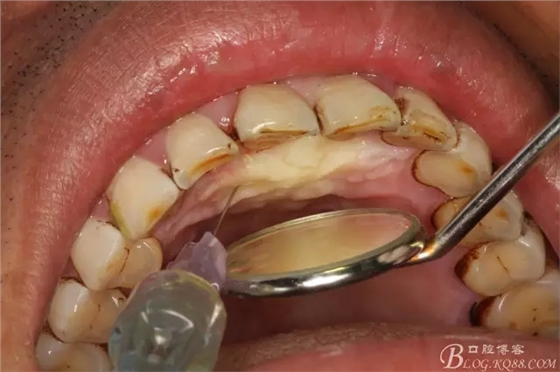

圖4.唇、腭側(cè)局部浸潤(rùn)麻醉